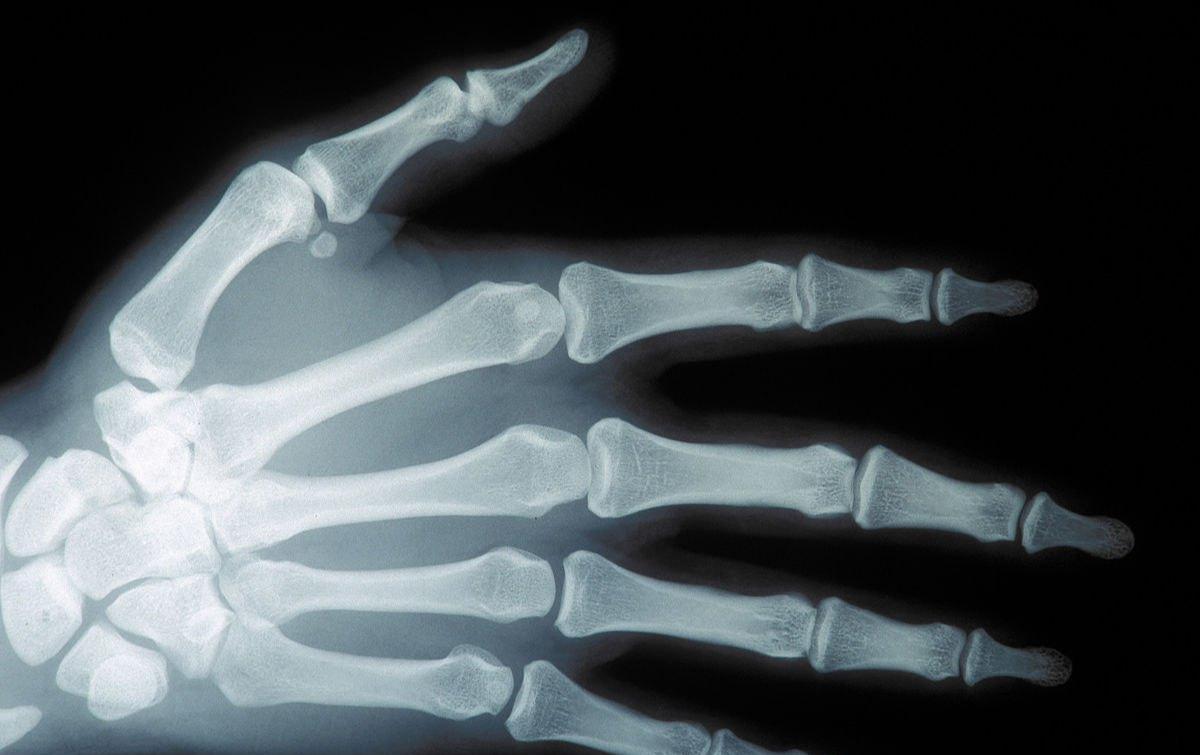

二、正中神经损伤,相应的体征有感觉障碍,以及肌肉障碍等

1、感觉障碍

若是患者受伤的部位是手腕,或者是前臂的肌肉,那么可能会导致感觉障碍出现在桡侧手。

2、对指功能受限

手掌的大拇指,一般位于桡侧。若是患病的话,可能会出现大拇指不能外转,也不能面向掌心和对指。在某些正中神经完全损伤的病例中,由于解剖变异,拇指掌侧外展不能完全丧失,尺神经也不能完全替代,少数病例表现正常。

3、拇指出现屈曲

除了以上症状外,桡侧浅屈肌和深屈肌都有麻痹,所以拇指和食指不能主动屈曲。无法弯曲前手臂。